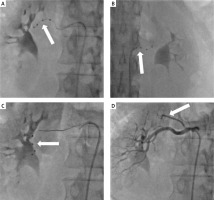

Figure 1

A, B – Initial renal artery denervation procedure (2020) using the Symplicity Spyral catheter in the right and left renal arteries (white arrows). C – Repeat renal artery denervation procedure (2021) using the Symplicity Spyral catheter in the right renal artery (white arrow). D – Right renal artery angiography showing the early polar branch of the right renal artery (white arrow)

RDN was performed using the Symplicity Spyral multi-electrode catheter (Medtronic, Minneapolis, MN, USA). Ten ablations of the left renal artery and fourteen ablations of the right renal artery were conducted (Figures 1 A, B). The procedure was uneventful. Post-procedure ABPM showed significant blood pressure reduction (mean value: 146/73 mm Hg, during the day 150/77 mm Hg, during the night 144/70). The patient was discharged with eight antihypertensive drugs: telmisartan (2 × 40 mg), bisoprolol (1 × 5 mg), amlodipine (1 × 10 mg), spironolactone (1 × 25 mg), torasemide (1 × 5 mg), indapamide (1 × 1.5 mg), doxazosin (1 × 4 mg), clonidine (3 × 225 μg).

Two months later, severe headaches returned, and ABPM revealed high blood pressure (mean value: 188/124 mm Hg, during the day 192/130 mm Hg; during the night 185/119 mm Hg). Hypertension therapy was modified: lisinopril (2 × 40 mg), bisoprolol (1 × 5 mg), amlodipine (1 × 10 mg), spironolactone (1 × 50 mg), torasemide (1 × 5 mg), indapamide (1 × 1.5 mg), doxazosin (1 × 8 mg), clonidine (3 × 225 μg). Due to the persistence of the symptoms and the initial significant decrease in blood pressure after RDN, a repeat procedure was indicated. The RDN procedure was performed using the Symplicity Spyral multi-electrode catheter. Eighteen ablations in the left renal artery and sixteen ablations in the right renal artery were performed during the second procedure (Figure 1 C). Blood pressure decreased significantly (ABPM mean value: 146/78 mm Hg, during the day 147/77 mm Hg; during the night 143/79 mm Hg). The patient was discharged with seven antihypertensive drugs: lisinopril (2 × 40 mg), bisoprolol (1 × 5 mg), amlodipine (1 × 10 mg), spironolactone (1 × 50 mg), torasemide (1 × 10 mg), indapamide (1 × 1.5 mg), doxazosin (1 × 8 mg).

Accessory renal arteries or early branches of the renal arteries and their incomplete denervation are associated with a lower RDN response rate. Additionally, patients with resistant hypertension have a higher prevalence of accessory renal arteries. Our patient did not have the early polar branch of the renal artery ablated due to its small diameter (Figure 1 D). Most of the clinical trials performed so far have not performed ablation in vessels < 4 mm in diameter [3, 4]. Precise patient selection appears crucial for improving RDN effectiveness [5].